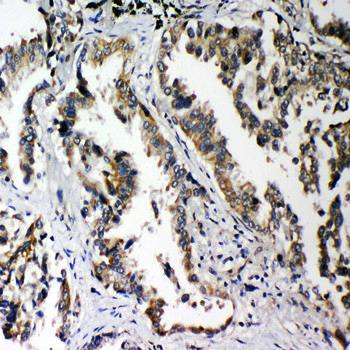

Immunohistochemical analysis of formalin-fixed paraffin embedded Rat Intestine Tissue using PLK2 antibody

Immunohistochemical analysis of formalin-fixed paraffin embedded Human Lung Cancer Tissue using PLK2 antibody